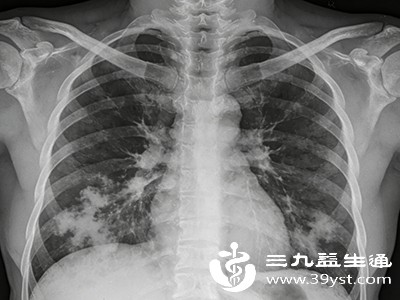

肺炎的症状 肺炎的5个常见发病症状

肺炎的症状